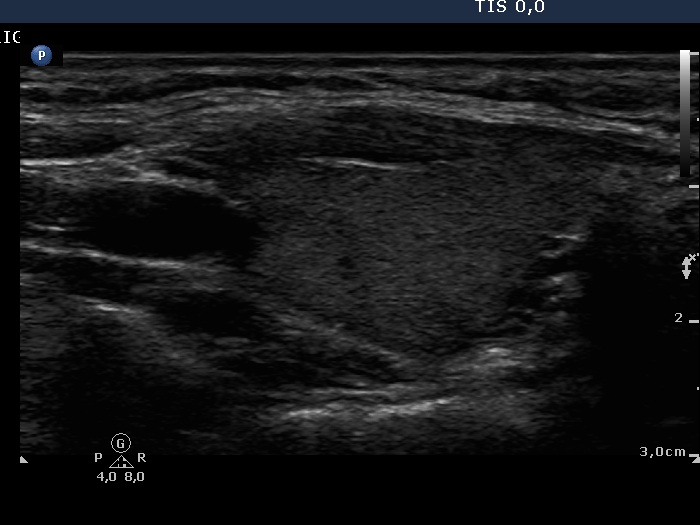

First examination (1st row of images)

Clinical data: A 29-year-old woman requested a second opinion. She was treated for Graves' disease for 2 months. The TSAb was initially 8.9 U/L, the FT4 was 54.2 pM/l. She get 30 mg methimazole therapy. Her complaints have already decreased.

Palpation: no abnormality.

Results of blood test: hyperthyroidism - TSH undetectable, FT4 29.2 pM/L, FT3 8.91 pM/L.

Ultrasonography: The thyroid was minimally enlarged and moderately hypoechogenic. The vascularization was a bit increased.

The dose of methimazole was reduced to daily 15 mg.